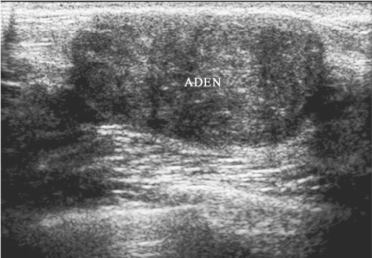

超声表现:①边界清楚,可见包膜;②一般为椭圆形,较大者可为类圆形,纵横比<1(图8-4);③内部回声与周边乳腺组织比较较低,细密而均匀;④后方回声增强,侧方声影明显;⑤直径较小时内部无钙化,直径超过3cm后有时可见少量较为粗大的钙化,并且可以出现液化;⑥同侧腋窝淋巴结无肿大;⑦CDFI:较小时基本无血流,偶见内部斑点状血流或周边环绕的细小血流,较大时内部可见中等偏少的血流,但走行自然,粗细均匀,血流异形性小。

图8-4 乳腺纤维腺瘤声像图